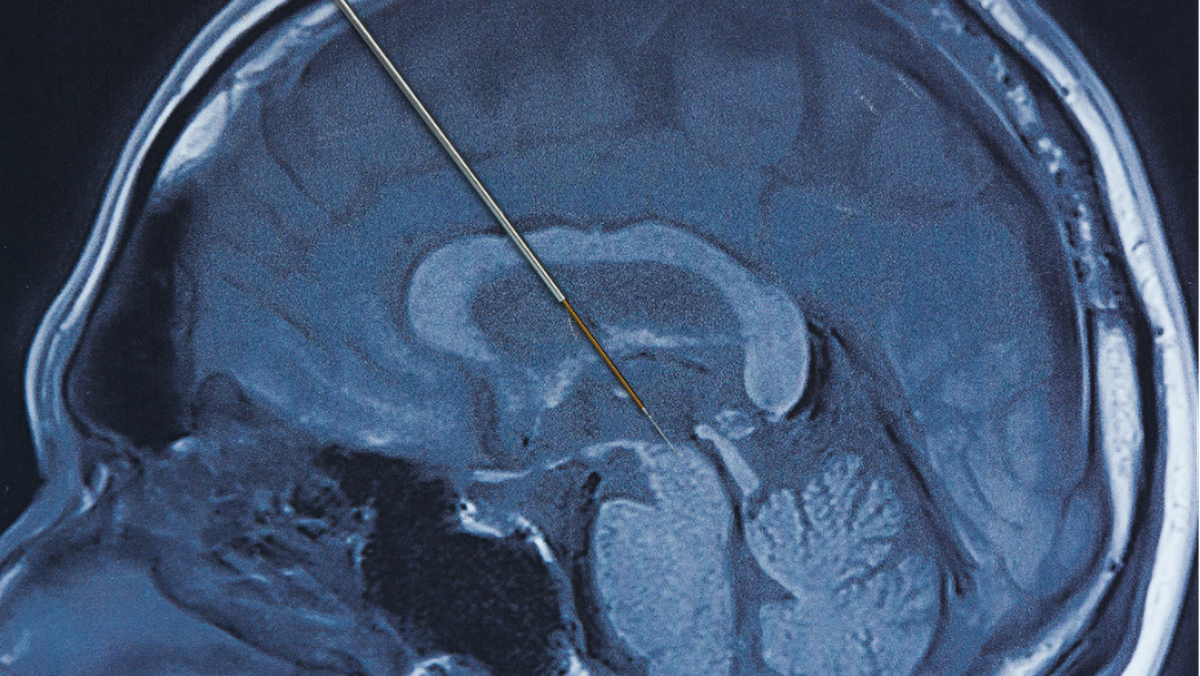

Deep brain stimulation merupakan prosedur bedah saraf yang melibatkan pemasangan elektroda Hingga area tertentu otak Sebagai Memberi rangsangan listrik terkontrol. Stimulasi ini bertujuan mengatur kembali sinyal saraf yang terganggu akibat Gangguan Parkinson.

Ahli Kemakmuran spesialis saraf Hingga Siloam Hospitals Kebon Jeruk, dr. Frandy Susatia, Sp.S, RVT, menjelaskan bahwa elektroda tipis ditanam Hingga otak dan dihubungkan Hingga Gadget stimulasi menyerupai alat pacu jantung. Gadget ini dipasang Hingga bawah kulit dada Dibagian atas dan bekerja secara terus-menerus mengirimkan impuls listrik sesuai pengaturan Ahli Kemakmuran.

Tahap pertama adalah pemasangan elektroda Hingga otak Bersama bius lokal agar pasien tetap sadar. Ke tahap ini, Ahli Kemakmuran dapat Menimbang ketepatan lokasi elektroda Melewati simulasi yang diberikan, sambil pasien diminta Sebagai Memberi umpan balik Yang Berhubungan Bersama perubahan Tanda yang dirasakan. Sesudah lokasi dan jumlah stimulasi yang optimal ditemukan, proses pemasangan Gadget DBS secara permanen Akansegera dilakukan.

Tahap kedua dilakukan Bersama bius umum Sebagai menanam Gadget stimulasi permanen Hingga bawah kulit dada Dibagian atas. Elektroda Hingga otak Lalu dihubungkan Hingga Gadget tersebut Melewati kabel halus yang dipasang Hingga bawah kulit.